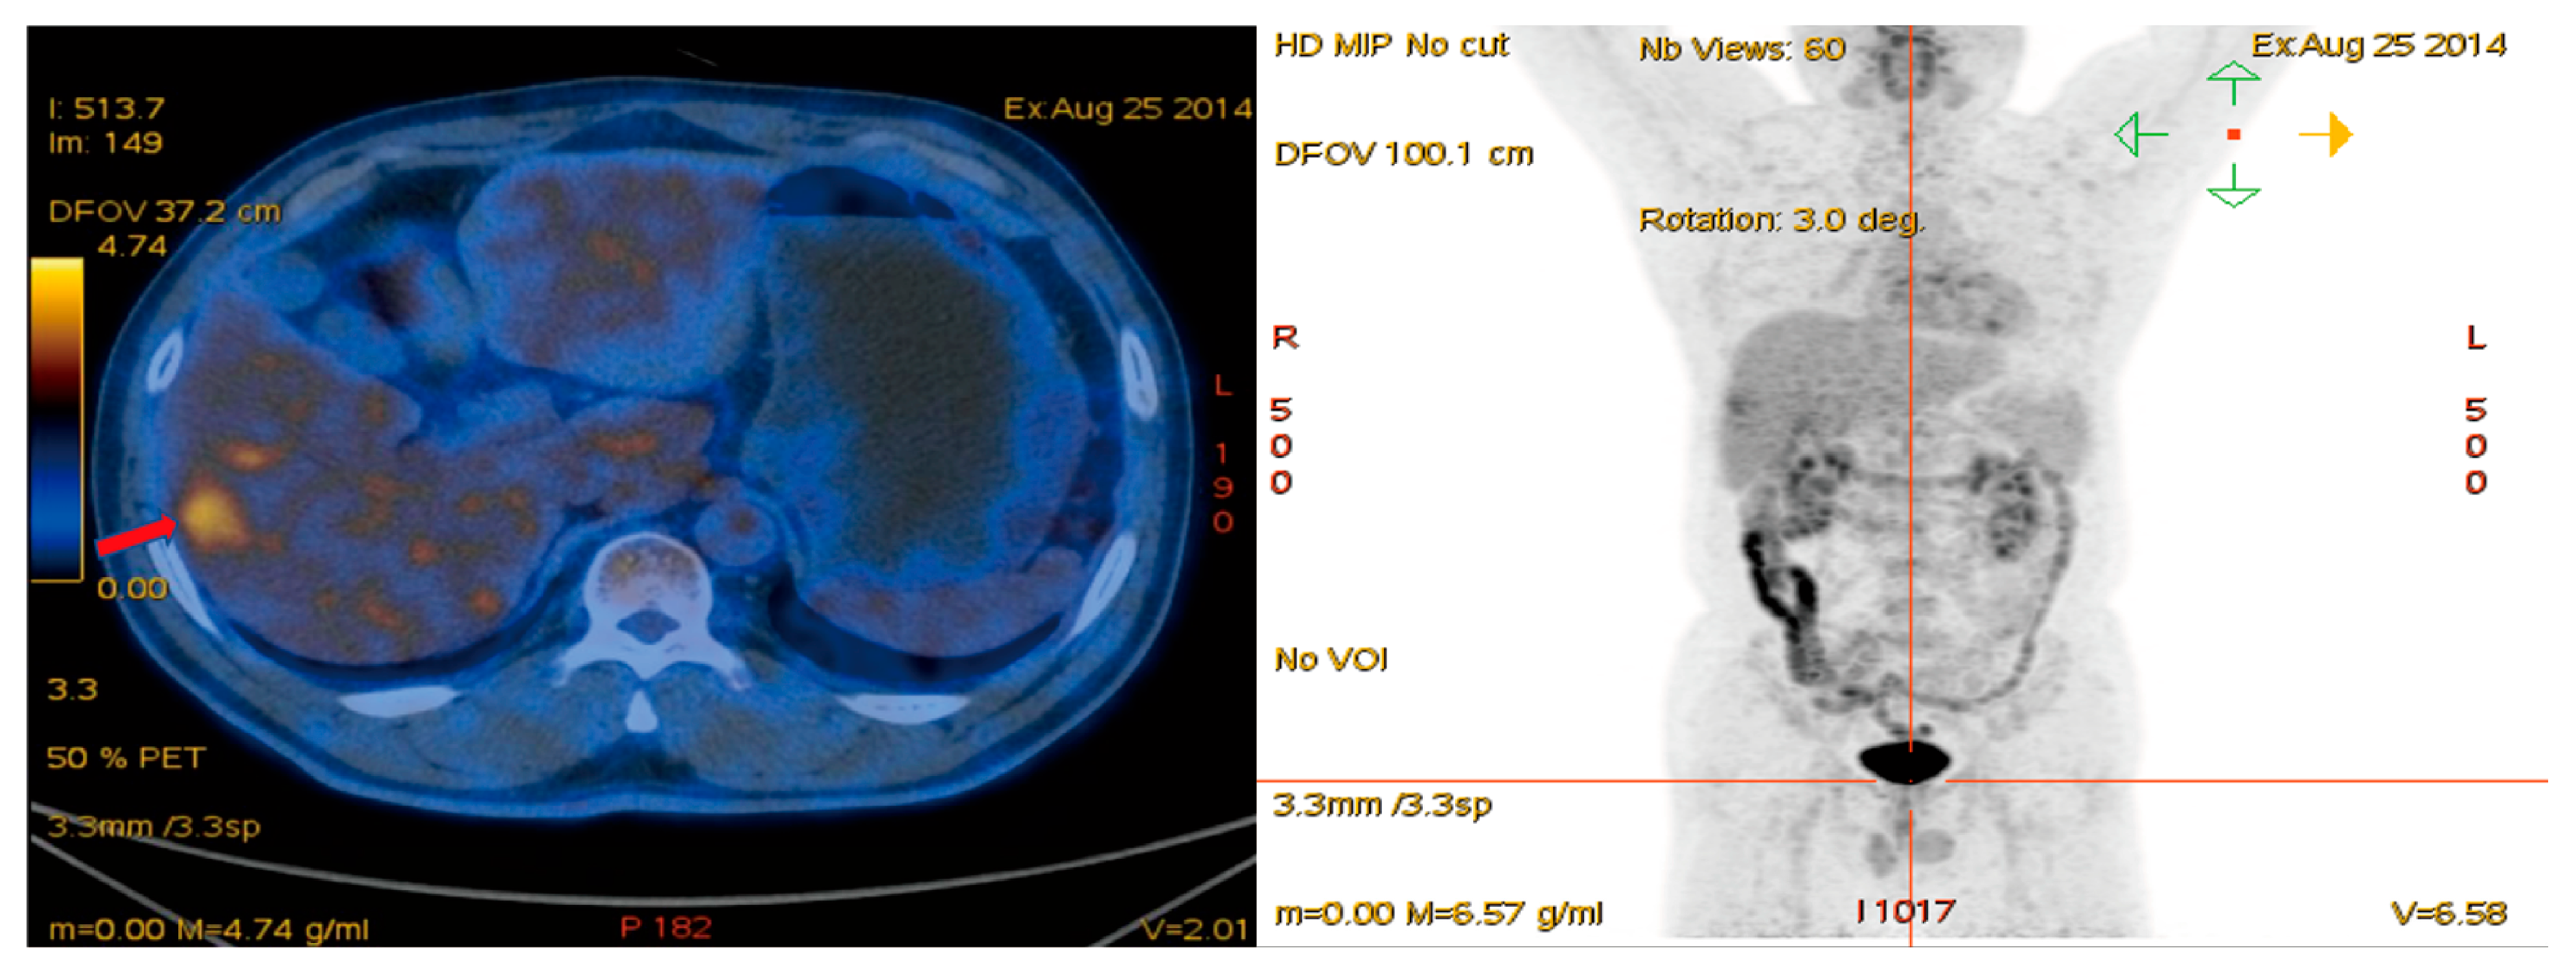

2.2. PET/CT and Research Indicators

| TSUVmax, mean | 6.04 ± 3.08 |

| LSUVmean, mean | 2.42 ± 0.47 |